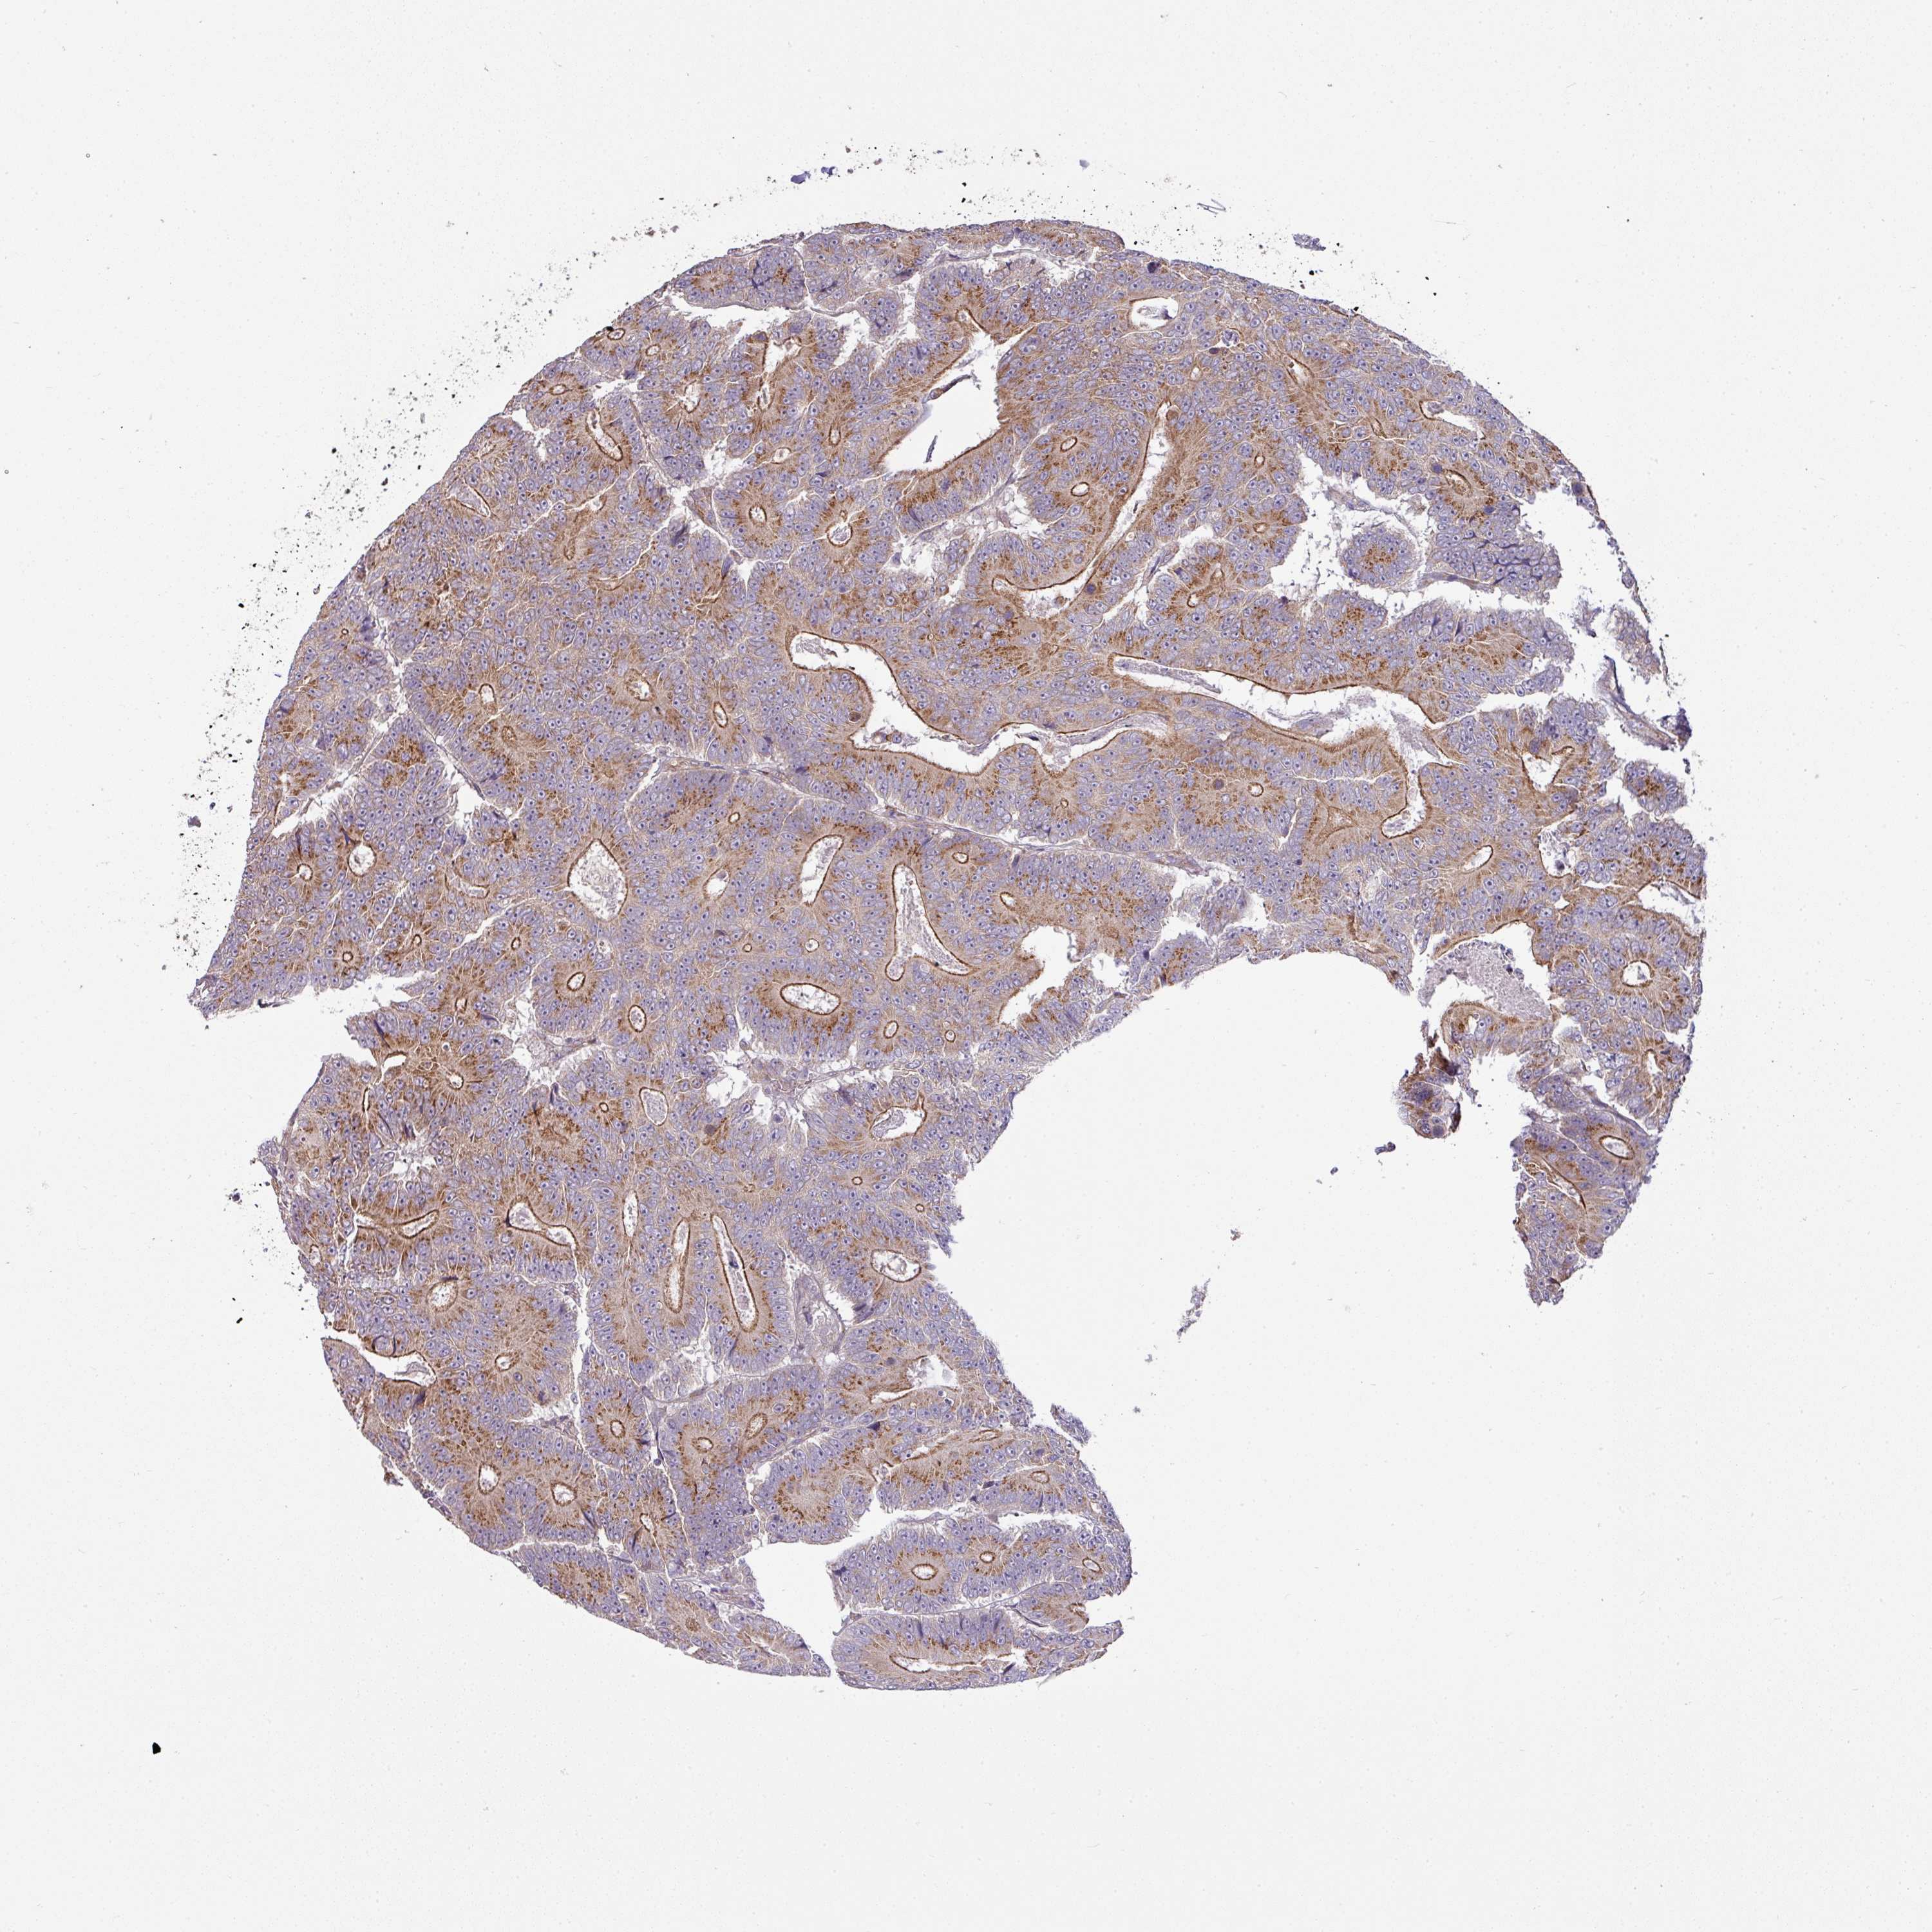

CANCER COLORECTAL CANCER Show tissue menu

Colorectal cancer

Colon adenocarcinoma